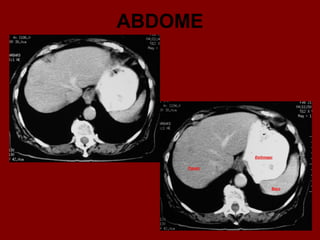

ABDOME